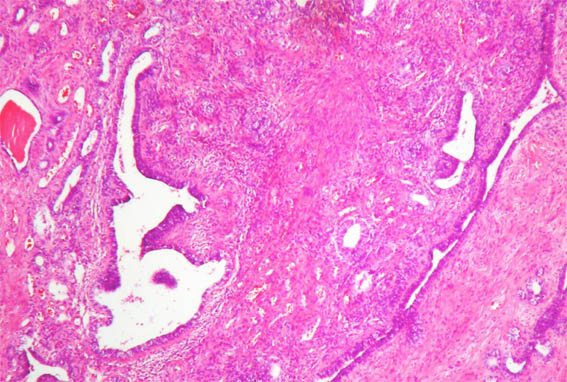

In a 44-year-old woman was incidentally detected, by ultrasound, a renal mass of 3.0 cm of diameter in the upper pole of the left kidney. She had cholelithiasis, with no other clinical alterations. Renal function tests and urinalysis were normal.

Nephrectomy was performed. We receive the case in consultation. See the images:

Figure 3. H&E, X100.